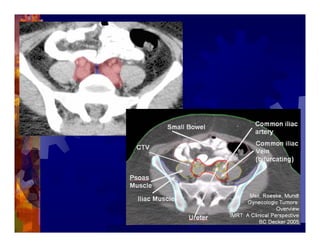

1) Intensity modulated radiation therapy (IMRT) is a technique that uses computer software to conform the radiation dose to the shape of the tumor, reducing dose to surrounding normal tissues and decreasing toxicity. 2) Numerous studies have shown IMRT provides better sparing of the small bowel, bladder, and rectum compared to conventional radiation for gynecologic cancers. 3) IMRT may allow dose escalation to high risk sites or involved nodes while maintaining normal tissue doses. Some studies have also investigated using IMRT as an alternative to brachytherapy boosts. 4) Clinical studies suggest IMRT results in low rates of acute gastrointestinal and genitourinary toxicity compared to conventional radiation for